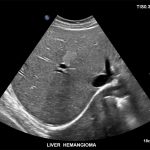

Imagini clinice:

Aplicatii: